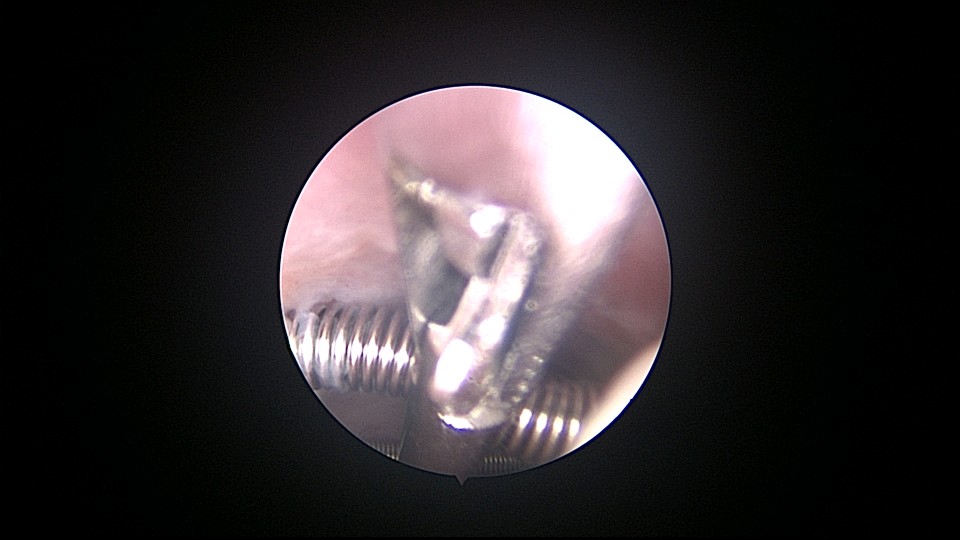

患者56岁,G4P1,顺产1次。1990、1991、1992年三次安环,均自然脱落,1993年第4次安环至今,共31年。现绝经4年,外院取环失败。患者阴道、宫颈、子宫萎缩,宫颈外口无法夹持,探针、中弯钳均无法打开宫颈外口,一筹莫展多时。最后用缝线缝住宫颈11点位及1点位,牵拉宫颈,尖刀片十字切开宫颈外口,B超监护下宫腔镜艰难进入宫颈管,见宫颈管封闭粘连,宫颈内口左侧粘膜下肌瘤遮挡视野。多次努力,镜子成功进入宫腔,见O型环两侧与子宫肌壁嵌顿,异物钳牵拉几次失败,用取环钩钩取,多次尝试终于成功钩住环,牵拉到宫颈外口,用中弯钳取出节育环,环变形,宫壁见节育环割裂痕迹,宫腔少许积血,无其他异常。